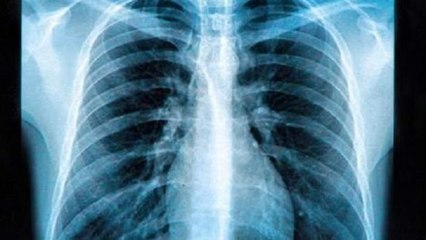

Der langjährige Bundesliga-Trainer Christoph Daum hat Krebs. Das gab der 68-Jährige am Freitag auf Instagram bekannt. Im Rahmen einer routinemäßigen Untersuchung sei bei ihm Krebs festgestellt worden, betonte Daum. „Seitdem befinde ich mich bei Prof. Dr. Jürgen Wolf und dem Team des CIO Köln in den besten Händen und bin froh, dass die Behandlung bei mir sehr gut anschlägt!“, so Christoph Daum via Instagram.